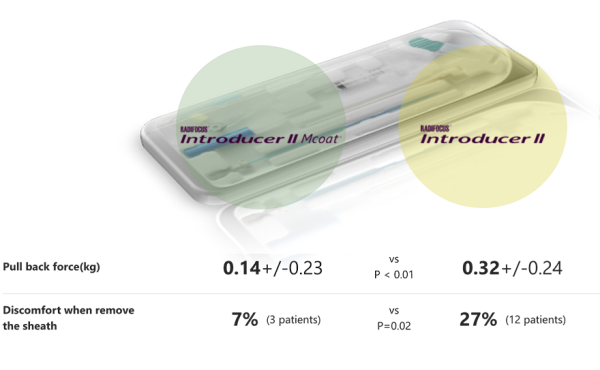

- I’m concerned about spasms during radial access for complex PCI.

How can I mitigate the risk? - Talking to the patient, helping them feel at ease, coupled with a good local anesthetic can contribute to lower spasm risk.

There’s also data to suggest that a hydrophilic-coated sheath can be effective too.Image 1: Avoiding excitement of the sympathetic nerves reduces somewhat the risk of

vasoconstriction.